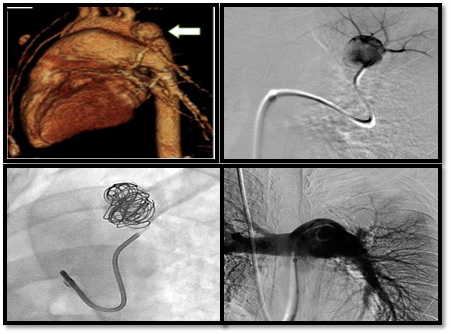

The aim of the procedure is to stop the blood flowing into the arteries which are responsible for haemoptysis while preserving blood flow to the normal surrounding area. The interventional radiologist will insert a less than 2 mm tube into your groin and will guide it under imaging to the affected blood vessel. Small resin particles (microparticles) will be inserted into the bleeding abnormal vessel or vessels in case of bronchial arteries. This causes the vessel or vessels to become blocked and so stops the bleeding. In case of pulmonary artery pathology coils, vascular plugs or liquid embolic agent may be used.